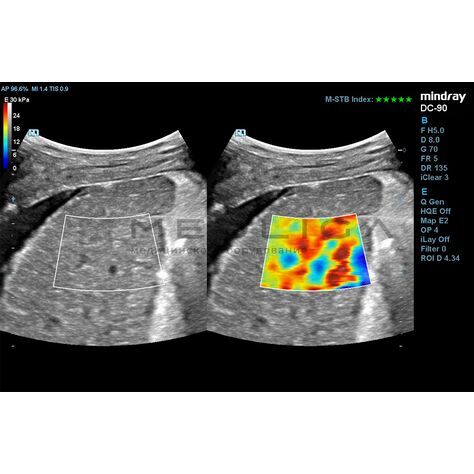

Программное обеспечение для оценки эластичности ткани методом эластографии сдвиговой волны (метод 2D-с формированием двухмерной цветовой эластограммы и количественной оценкой эластичности) на линейных и конвексных датчиках.

STE интегрирована с эксклюзивной технологией Ultra-Wide Beam Tracking от Mindray для двумерной эластографии сдвиговой волной в реальном времени. Специализированные измерительные инструменты позволяют проводить количественный анализ модуля упругости с высокой точностью.

Опция работает:

• на линейных датчиках

• на конвексных датчиках